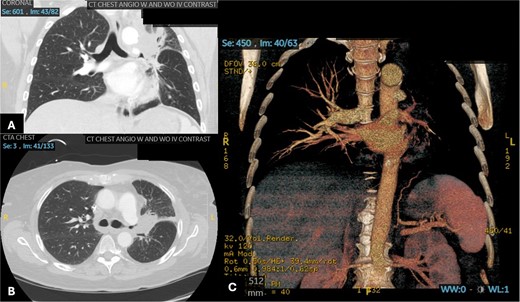

A 60-year-old woman with acute lymphoblastic leukemia recently started on chemotherapy presented to the emergency department with a dry cough that later progressed to a productive cough with green sputum. Exam was largely unremarkable as patient was afebrile and had normal lung auscultation. Initial infectious work-up, including bacterial, fungal and mycobacterial cultures, fungal serum and urine antigens, and COVID-19 testing were negative. Given a negative infectious work-up, a CT chest, abdomen, and pelvis was obtained revealing a 5 cm perihilar mass causing complete obliteration of the left pulmonary artery and minimal-to-no perfusion to the left lung (Fig. 2).

Patient 2 pre-operative images. (A) Coronal section of CT angiogram showing LUL mass abutting the aortic arch and invading the left main pulmonary artery and left mainstem bronchus. (B) Axial CTA showing complete occlusion of the left pulmonary artery. (C) 3D reconstruction of CTA showing complete occlusion of the left pulmonary artery and lack of opacification of any pulmonary artery branches and pulmonary oligemia.

A bronchoscopy was completed for biopsy of the lesion and revealed angioinvasive mucormycosis. The patient was immediately started on amphotericin and isavuconazole and evaluated by thoracic surgery for possible surgical resection. Given the perihilar location involving the pulmonary artery, it was likely that a pneumonectomy would be required. Pulmonary function tests (PFTs) were completed and showed an FEV1 of 54% predicted and diffusing capacity of the lungs for carbon monoxide (DLCO) of 57% predicted. Although these PFTs alone suggest that a pneumonectomy may not be tolerated; it is important to note that on the CT scan there was no perfusion to the left lung. A V/Q scan confirmed absent perfusion to the left lung given the invasion of the pulmonary artery with only 3.4% of perfusion reaching the left lung. Therefore, a pneumonectomy would not change PFTs significantly.